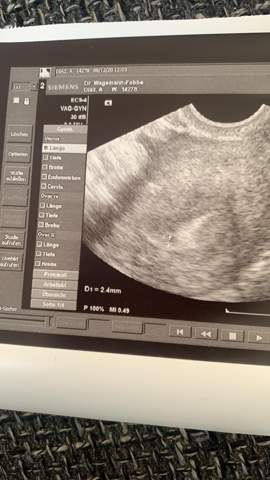

Jetzt bin ich schon heute 12 Tage drüber und weiss nicht ab wann ist ein Test wirklich sicher mit dem Ergebnis da ich ja 5 Tage. Eine optimal aufgebaute Schleimhaut zeigt im Ultraschall drei Linien. Proliferationsphase eine gut aufgebaute Schleimhaut hat zwei Bedeutungen.

Vielleicht kennst du schon meinen Artikel zum Aufbau der Gebärmutterschleimhaut hier und weißt deshalb dass eine gut aufgebaute Schleimhaut vor dem Eisprung mindestens 7 mm hoch sein sollte. FÄ sagt hoch aufgebaute schleimhaut nicht schwanger da ist eine Zyste die kann Hormone abgeben. Ich würde in der Zeit am liebsten gar nix testen oder messen oder sonst was. 3 Linien im Ultraschall. Entweder die baldige Mens oder eben eine SS. Ok dass ich am Eierstock eine Zyste habehatte wusste ich. Neben der Dicke der Schleimhaut ist aber besonders deren Aufbau wichtig. Man ist schwanger 2. Vielleicht kennst du schon meinen Artikel zum Aufbau der Gebärmutterschleimhaut hier und weißt deshalb dass eine gut aufgebaute Schleimhaut vor dem Eisprung mindestens 7 mm hoch sein sollte.